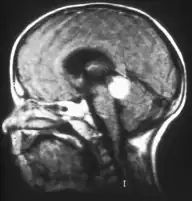

Aspect of trilateral retinoblastoma on MRI -

Inherited forms of retinoblastomas are more likely to be bilateral. In addition, inherited uni- or bilateral retinoblastomas may be associated with pineoblastoma and other malignant midline supratentorial primitive neuroectodermal tumors (PNETs) with a dismal outcome; retinoblastoma concurrent with a PNET is known as trilateral retinoblastoma.[17] A 2014 meta-analysis showed that 5-year survival of trilateral retinoblastoma increased from 6% before 1995 to 57% by 2014, attributed to early detection and improved chemotherapy.[18]

In about two-thirds of cases,[29] only one eye is affected (unilateral retinoblastoma); in the other third, tumors develop in both eyes (bilateral retinoblastoma). The number and size of tumors on each eye may vary. In certain cases, the pineal gland or the suprasellar or parasellar region (or in very rare cases other midline intracranial locations) is also affected (trilateral retinoblastoma). The position, size, and quantity of tumors are considered when choosing the type of treatment for the disease.